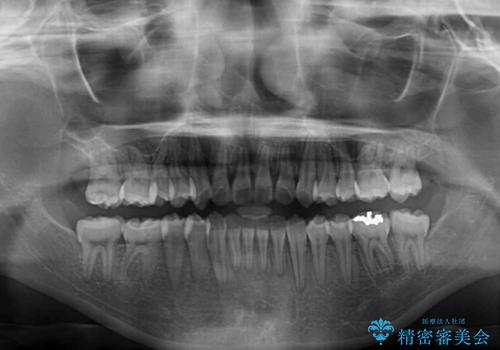

急速拡大装置を用いて上顎骨を側方に拡大し、上顎の叢生を解消するとともに下顎歯列拡大により下顎の叢生も解消することとしました。

急速拡大装置使用直後は著しいスペースが正中に発現するため、ワイヤー矯正を行いますが、今回は治療期間を短くしたいとのことで、上下全体をワイヤー装置にて矯正治療することとしました。

上顎骨を拡大しない場合には、奥歯に咬みにくさが残ったり、下顎前歯の歯肉退縮や口元の突出感などが出たりと、妥協的な仕上がりとなります。